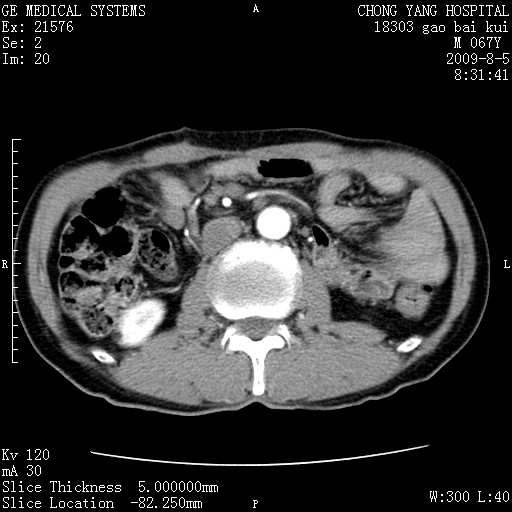

这个也过了,考虑胰腺钩突癌或壶腹癌,不除外胰管粘液乳头瘤伴胰管扩张,肝内胆管积气.

1)考虑胰头癌或壶腹癌并胰管扩张。2)肝外胆管扩张、积气,胆囊影未见;考虑术后改变。3)胃壁增厚?建议必要时行胃镜检查。

虑胰腺钩突癌或壶腹癌,不除外胰管粘液乳头瘤伴胰管扩张,肝内胆管积气.

考虑胰头癌并十二指肠受侵。